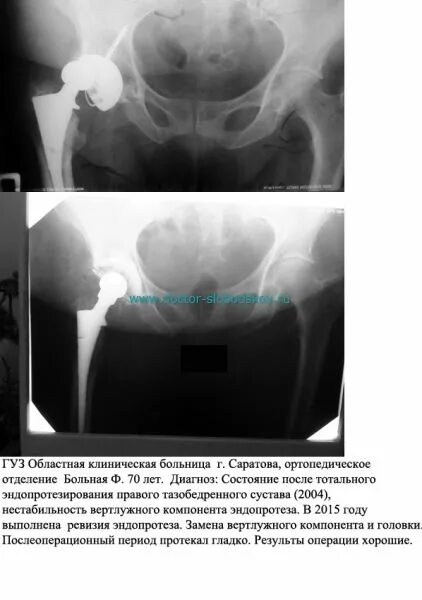

Эндопротезирование тазобедренного сустава после 3 месяцев